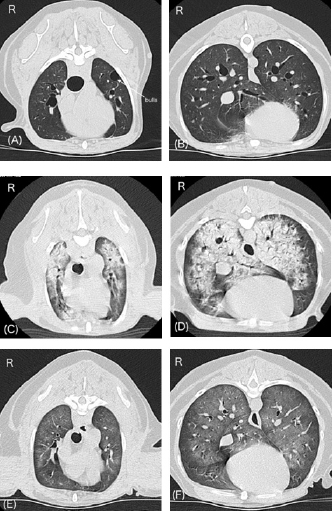

The dog was scheduled to undergo contrast-enhanced computed tomography (CT) with 300 mg iodine/ml iohexol (Omnipaque 300 injection; Daiichi Sankyo Co., Ltd., Tokyo, Japan) at 2 ml/kg for surgical planning of adrenalectomy 7 days after the initial examination at our hospital. A 22-gauge, 31-mm intravenous (IV) catheter (Supercath5; Medikit Co., Ltd., Tokyo, Japan) was placed in the cephalic vein, and general anesthesia was induced with IV administration of butorphanol (Vetorphal; Meiji Animal Health Co., Ltd., Tokyo, Japan) and propofol (PropoFlo; Zoetis Japan, Tokyo, Japan). After intubation, anesthesia was maintained using oxygen and isoflurane (Isoflu; Zoetis Japan, Tokyo, Japan). The electrocardiogram, pulse rate, RR, end-tidal carbon dioxide concentration, indirect mean arterial pressure (MAP), and percutaneous oxygen saturation (SpO2) were monitored using a multiparameter monitor (BSM-5192; Nihon Kohden Corporation, Tokyo, Japan). During the CT scan (Aquilion PRIME; Canon Medical Systems Corporation, Tochigi, Japan), intermittent positive pressure ventilation was maintained. The patient’s pulse rate ranged from 58 to 79 beats/minute, and MAP ranged from 68 to 79 mmHg during anesthesia. The time from the induction of anesthesia to extubation was 24 minutes, and recovery from anesthesia seemed to be very smooth. The dog was moved to the ward after spontaneous head lift was observed. CT scans showed a right adrenal gland mass invading the caudal vena cava (Fig. 1). In addition, the mass around the celiac and cranial mesenteric arteries was consistent with a previous report of paraganglioma (Gombert et al., 2022) (Fig. 1). The CT images of the lungs appeared normal, except for some bullae (Fig. 2A and B).

Approximately 15 minutes after being moved to the ward, the dog exhibited dyspnea and nose bleeding. The oral mucous membrane was pale, systolic blood pressure was >200 mmHg, and SpO2 ranged from 70% to 80%. The pulse rate was not recorded. A catecholamine crisis was suspected, and IV acepromazine (PromAce injectable; Boehringer Ingelheim Animal Health, Ridgefield, CT) at 0.01 mg/kg was administered for vasodilation and sedation. In addition, oxygen supply via a mask or flow-by was initiated after upper airway suctioning of blood and secretions. Following these treatments, the patient’s blood pressure decreased. Systolic and mean blood pressures were 140 and 100 mmHg, respectively. However, SpO2 remained at approximately 90% despite oxygen therapy, and respiratory distress was evident. Lung ultrasonography (LOGIQ e Premium; GE HealthCare, Tokyo, Japan) revealed a shred sign suggestive of lung consolidation with aeration in the left caudodorsal and perihilar lung regions. Multiple B lines suggestive of a wet lung were also observed in the left lung. The awake CT images taken 90 minutes after anesthetic recovery showed severe pulmonary consolidation with air bronchograms throughout all lung fields (Fig. 2C and D), and a decision was made to initiate ventilatory support under stable hemodynamics. Blood sampling for measurement of plasma catecholamine levels could not be performed given that our top priority was to stabilize a critical hypoxemia following the hypertensive crisis.

Fig. 2. Changes in lung CT images over time. A and B, images with breath hold at 10 cm H2O under general anesthesia before a hypertensive crisis. C and D, awake images 75 minutes after the onset of respiratory failure following a hypertensive crisis. E and F, images under spontaneous breathing 24 hours after onset of respiratory failure. Panels A, C, and E, cranial level; panels B, D, and F, caudal level. A and B show normal canine lungs except for the presence of bulla. C and D reveal acute onset of severe pulmonary consolidation with air bronchograms throughout all lung fields compared with A and B. E and F reveal dramatic improvement of pulmonary consolidation compared with C and D.

On the morning after 14 hours of ICU ventilation, PaO2 and PaCO2 were 93 and 33 mmHg, respectively. The P/F ratio was calculated to be 310. The ventilatory settings were: ΔPsupport, 7 cm H2O; CPAP, 5 cm H2O; and FiO2, 0.3. No cardiorespiratory instability was observed. In addition, only a few B lines were observed on lung ultrasonography. Improvement in the pulmonary CT images was also noted (Fig. 2E and F). Therefore, an attempt to wean the patient from the ventilator was initiated 15 hours after starting ICU ventilation (24 hours after the onset of respiratory failure). To allow weaning from the ventilator, constant-rate infusions were discontinued. Ten minutes later, the patient was no longer accepting the endotracheal tube, at which time the patient was extubated. Blood sputum adhesion was observed at the tip of the extubated tube. The patient was able to breathe effectively with some respiratory effort, and SpO2 was 96% under nasal oxygen supply at 0.5 l/minute. PaO2 and PaCO2 were 77 and 27 mmHg, respectively. The body weight after weaning was 170 g less than that before the onset of respiratory failure. Cefazoline and enrofloxacin (Baytril 2.5% injection for dogs and cats; Elanco Japan, Tokyo, Japan) were administered as prophylactic antibiotics during hospitalization. In addition, oral treatment with pimobendane (VETMEDIN chewable tablet; Boehringer Ingelheim Animal Health, Tokyo, Japan) was resumed. Oxygen therapy was continued for 24 hours after extubation. Finally, the dog was discharged 3 days after weaning from ventilation. The owner refused additional treatment for the intra-abdominal lesions. The dog survived without any respiratory or neurological complications for 14 months after weaning from mechanical ventilation.